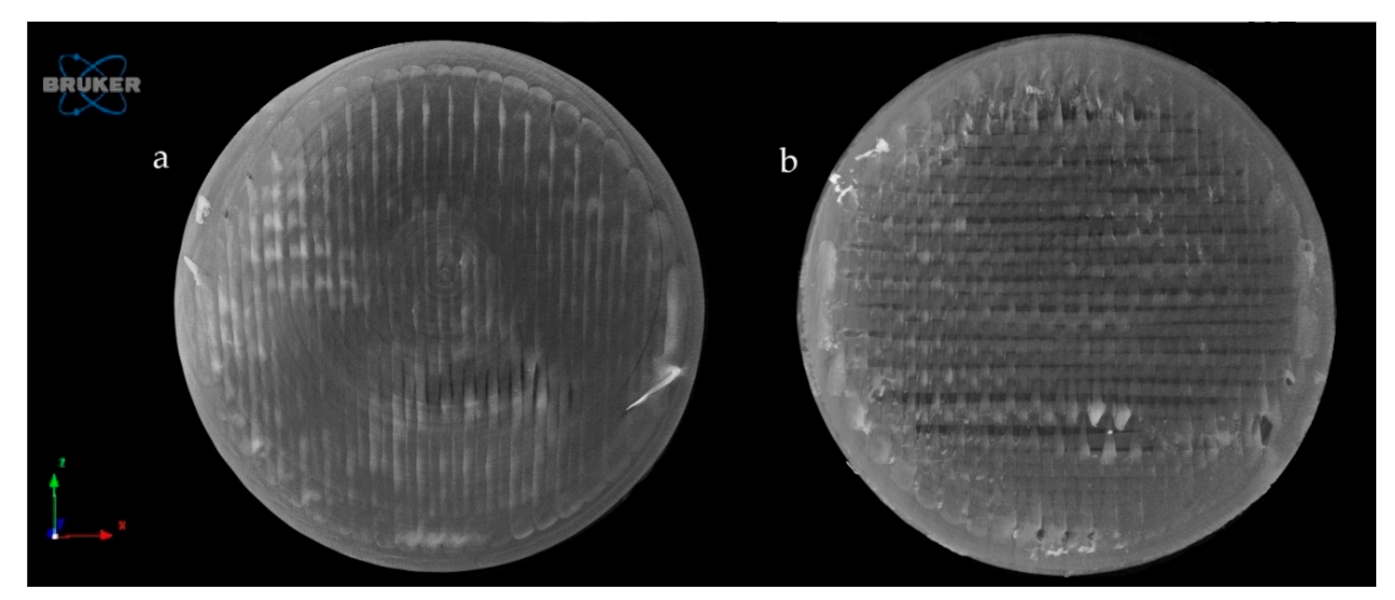

2.4.4. Microcomputed Tomography (MicroCT)

Microcomputed Tomography (MicroCT)